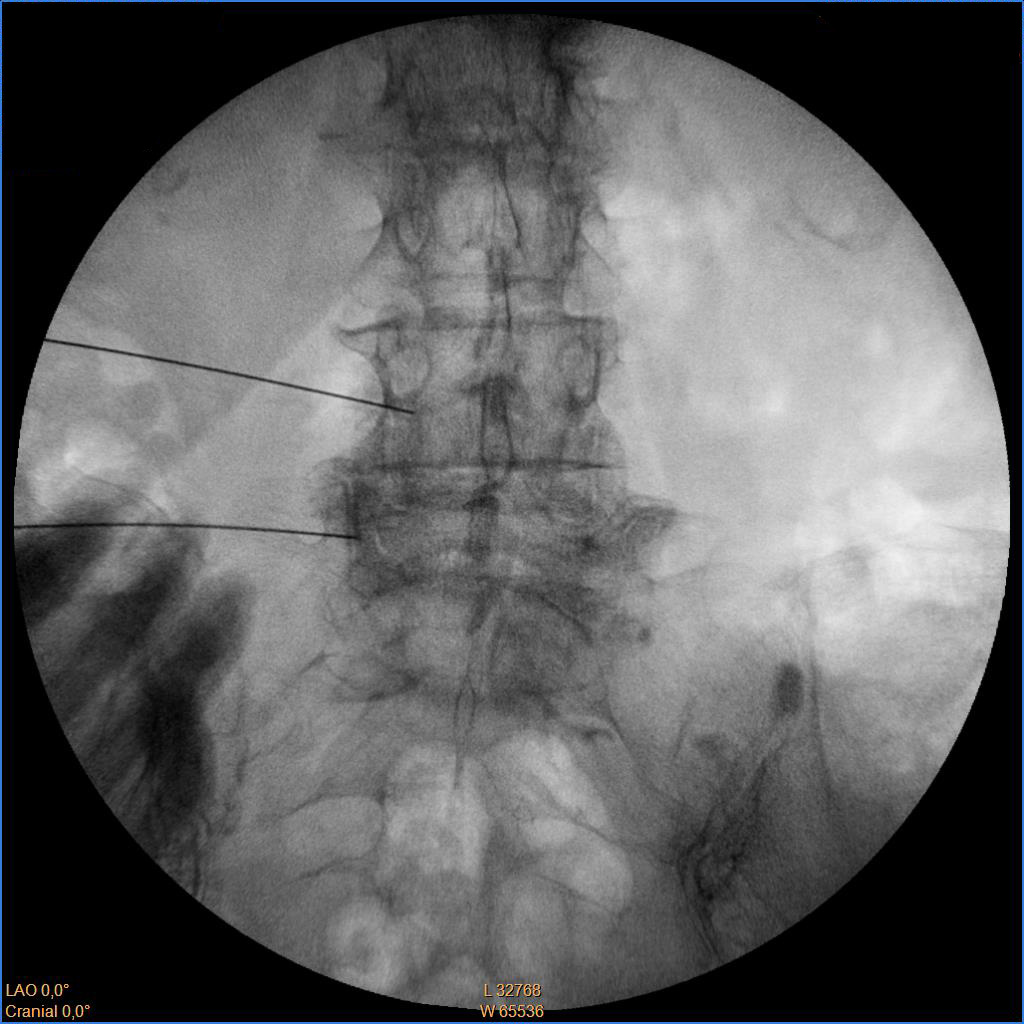

Ασθενής με σπονδυλαρθρίτιδα και 2 δισκοκήλες

Ασθενής 86 ετών με έντονο άλγος οσφύος, αντανάκλαση στο κάτω άκρο και αιμωδίες αριστερού άκρου ποδός απο 2μήνου λόγω σπονδυλαρθρίτιδας και 2 δισκοκηλών σε 2 επίπεδα. Με τοπική αναισθησία τοποθέτηση 2 βελόνων.  Έλεγχος σωστής τοποθέτησης με χρήση σκιαστικού και εισαγωγή μείγματος αναλγητικών. Άμεση ανακούφιση με αποτέλεσμα που διατηρείται 1.5 χρόνο μετά.